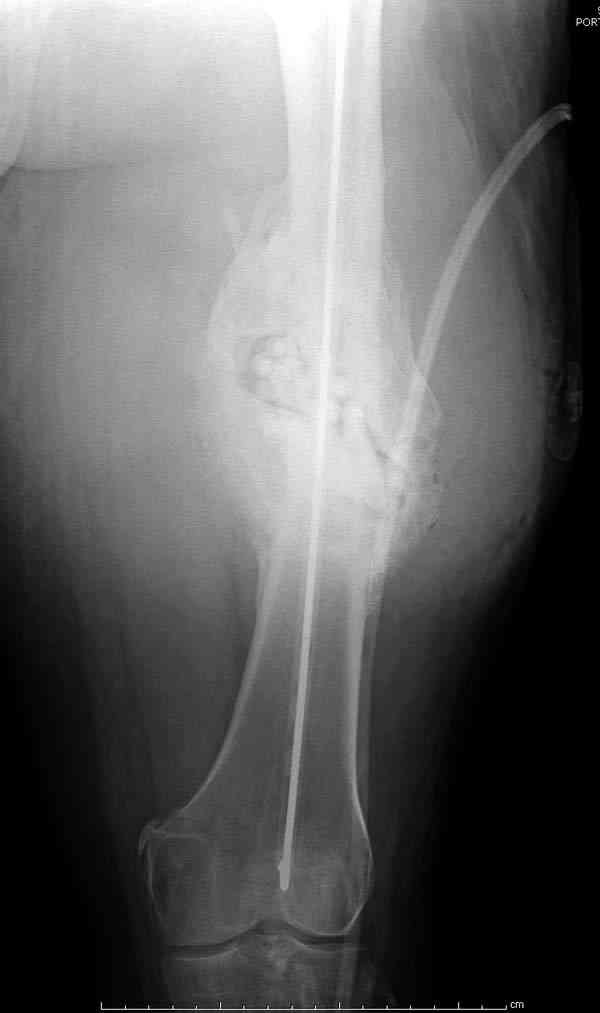

На ренгенограмме явный остеомиелит с секвестром, секвестерэктомия из медиального доступа и замена старого антибиотического гвоздя на новый.

После трех дней ваккуумного дренажа, из латерального доступа удаление остатков старых антибиотичеких бус, закрытие медиальной раны с наложением ваккуумирования латерально. В следующий раз, через пару дней надеемся закрыть рану.

подготовка гвоздя

7-8 послеоперационные